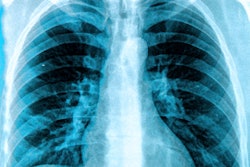

A group of Italian researchers found the performance of radiologists for detecting COVID-19 pneumonia on chest x-rays grew over time as they gained experience -- a finding that even applied to those with less experience reading x-rays. They shared their results online September 10 in the European Journal of Radiology.

After retrospectively assessing the diagnostic performance of chest x-rays performed at their university hospital during the height of the pandemic, a team of researchers led by first author Dr. Andrea Cozzi and senior author Dr. Francesco Sardanelli of the University of Milan found that the radiologists with less than 10 years of experience reading chest x-rays yielded the same 89% sensitivity level as a group with more-experienced radiologists.

Although the most-experienced radiologists produced higher specificity, both groups improved their sensitivity and accuracy over the six weeks of the study.

"The increase in accuracy over time strengthens [chest x-ray's] role as a first-line examination in suspected COVID-19 patients," the authors wrote.